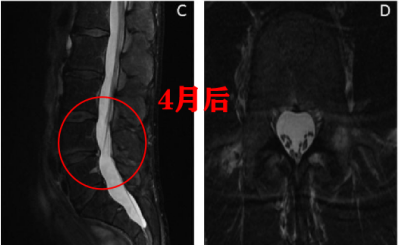

图一:LDH 患者 L4/5 在出现症状 5 个月后发生自发性消退

患者女,29 岁,因「右小腿疼痛并感觉异常」就诊,大小便正常。起始腰椎磁共振提示腰 L4/5 突出并椎管狭窄,神经根压迫严重(左图)。患者选择保守治疗,5 个月后复查 MRI(右图)发现突出的椎间盘自发性吸收了,并且临床症状基本缓解。